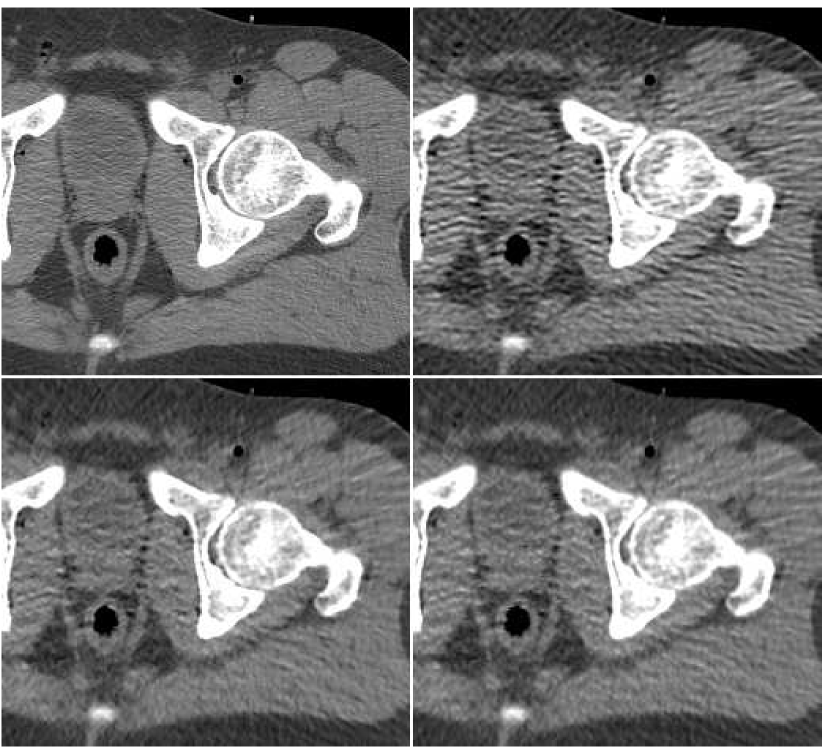

To summarize the fusion effect on the outcome of standard reconstruction algorithms, we display in Figure 12 images produced by both FBP and PWLS methods, before and after applying the proposed method of the ANN-based fusion; these images were previously given in Figures 6,10.

As a last experiment, we consider the special case where the ANN only performs a local filtering of the single version of the image, without a reference to the other versions. A neighborhood of radius ( pixels) was extracted for each location in the PWLS image, corresponding to iteration number . The fusion result is visually compared in Figure 14 versus the image produced from PWLS versions, as before. It can be observed that the processing by ANN reduces the noise appearing in the PWLS image, but it is slightly inferior to the fusion image produced from several PWLS versions.